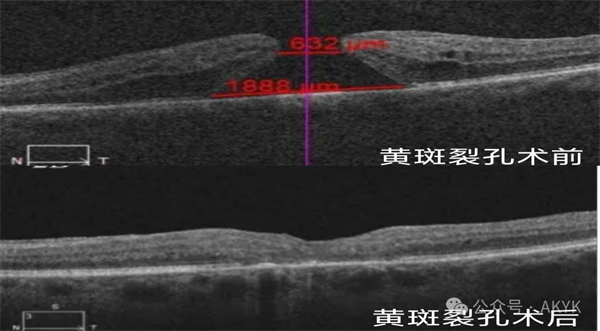

新業(yè)務(wù)二

復(fù)雜黃斑裂孔修復(fù)術(shù):修補裂孔提升視力,降低致盲率。